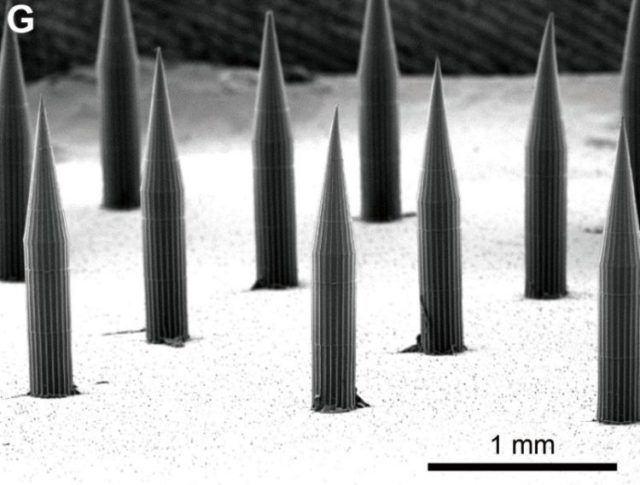

Die Größe der Nadeln sieht etwa so aus:

Statt mit einer urtümlichen Spritze bekommt man die Impfung dann per Pflaster in die Haut gedrückt. Die winzigen Nadeln sind aus einer Art löslichem Zucker und einem Polymer (PVA), dem Quantenpunktfarbsoff und sie enthalten den Wirkstoff, der sich mit den Nadeln im feuchten Milieu im Körper auflöst und im Körper verteilt.

Wenn das Pflaster auf die Haut aufgeklebt wird, lösen sich die 1,5 Millimeter langen Mikronadeln teilweise auf und geben ihre Nutzlast innerhalb von etwa zwei Minuten ab. Die kleinen Mikrokristalle lösen sich nicht auf, sondern verbleiben an der Stelle, wie QR-Punkte und können ausgelesen werden. Hier eine Darstellung aus dem Bericht des MIT: